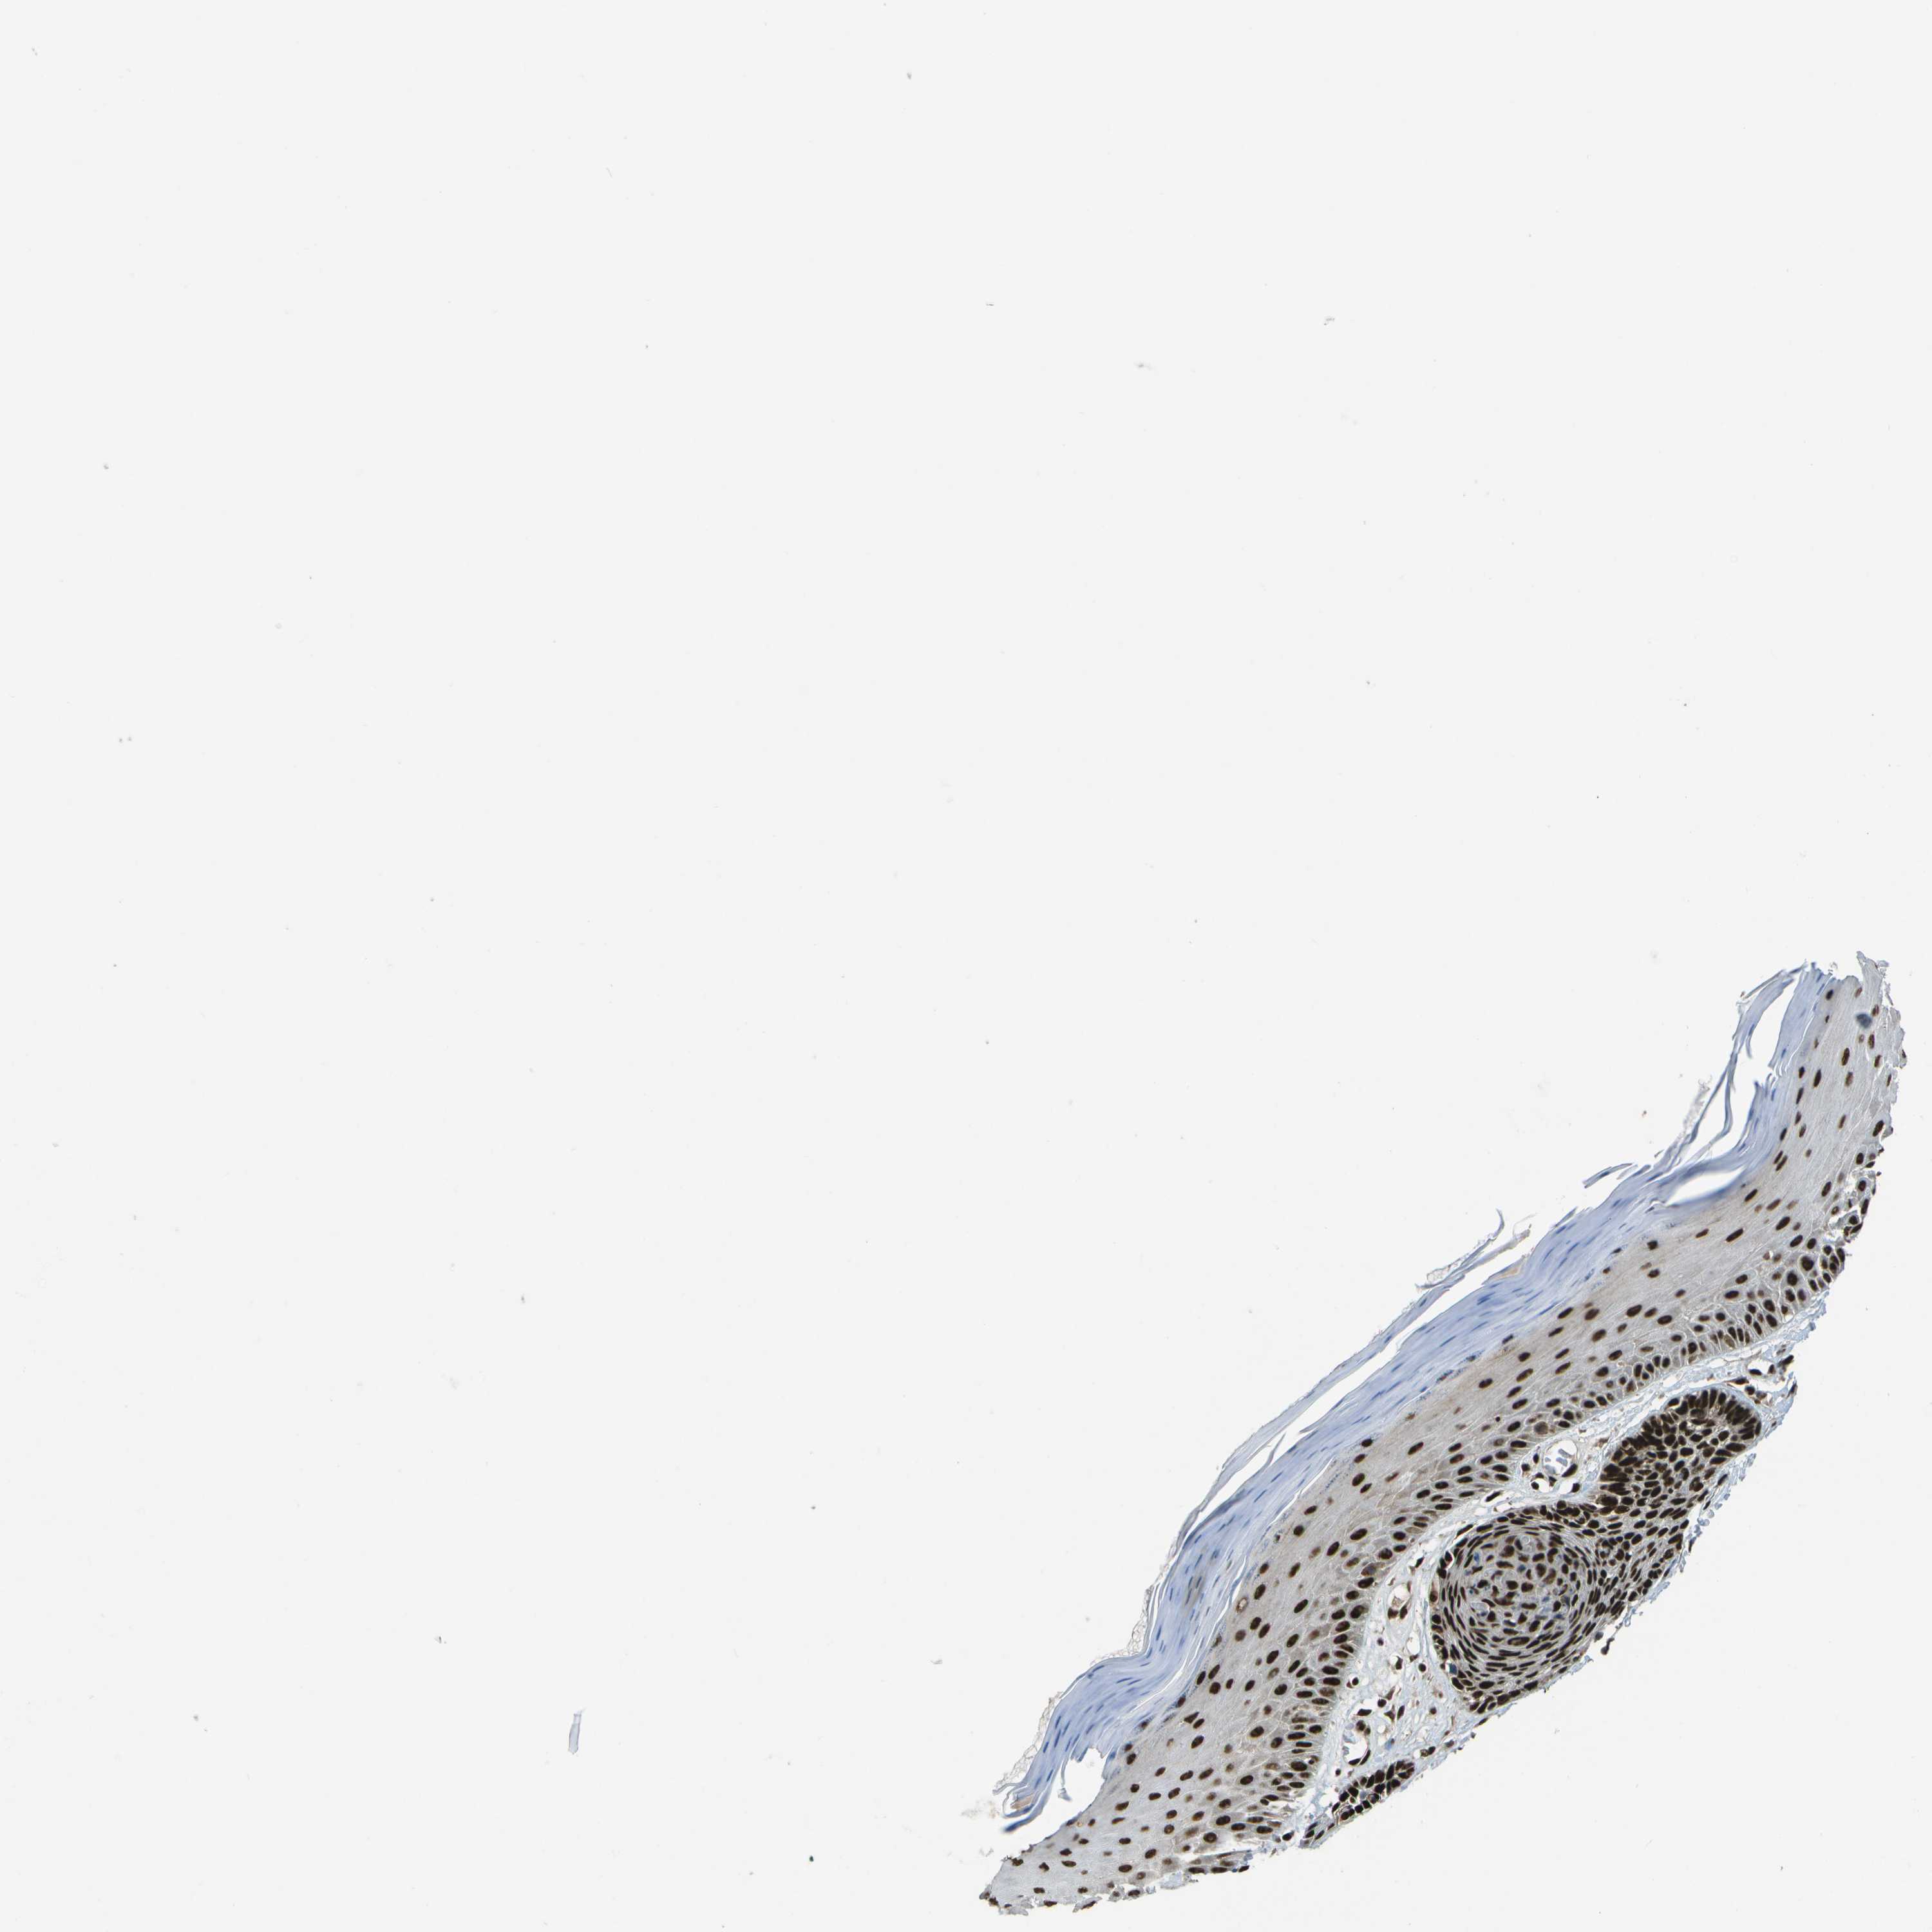

SKIN CANCER - Protein expressioni

A mouse-over function shows sample information and annotation data. Click on an image to view it in a full screen mode. Samples can be filtered based on level of antibody staining by selecting one or several of the following categories: high, medium, low and not detected. The assay and annotation is described here.

Antibody stainingi

Antibody staining in the annotated cell types in the current human tissue is reported as not detected, low, medium, or high, based on conventional immunohistochemistry profiling in selected tissues. This score is based on the combination of the staining intensity and fraction of stained cells.

Each image is clickable and will lead to virtual microscopy that enables deeper exploration of all samples and also displays staining intensity scores, fraction scores and subcellular localization as well as patient and tissue information for each sample.

Antibody HPA016949

Staining

High

Medium

Low

Not detected

Intensity

Strong

Moderate

Weak

Negative

Quantity

>75%

75%-25%

<25%

None

Location

Nuclear

Cytoplasmic/membranous

Cytoplasmic/membranous,nuclear

Squamous cell carcinoma in situ, NOS

Squamous cell carcinoma, NOS

Squamous cell carcinoma, metastatic, NOS

Basal cell carcinoma

Adnexal tumor, benign